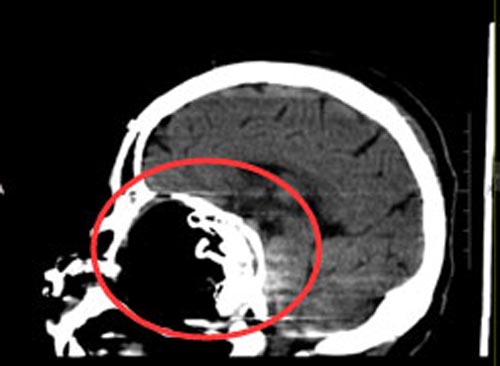

几十年间,视力由模糊不清变成了仅有光感,吕阿姨也一直没有再去医院。3年前她开始出现嗅觉丧失,近1个月来出现头痛,伴有鼻腔流液,吕阿姨和家人意识到病情严重了。当地医院头颅CT检查提示:“筛窦-蝶窦巨大囊肿”,广东三九脑科医院进一步头部MR检查显示:前颅底及筛窦-蝶窦-鼻咽部巨大占位病变,待排骨来源病变,骨化性纤维瘤可能,待排软骨来源肿瘤。

综合神经外科鲁明副院长了解病情后认为:患者前颅窝底及鼻腔巨大占位,考虑骨源性肿瘤;无手术禁忌症,家属同意行手术治疗。完善相关术前检查后,在全麻下“经右侧前颅窝额底硬膜外及鼻蝶联合入路前颅窝底及鼻腔巨大胆脂瘤切除术+颅底重建术+颅骨成形术”,手术顺利。术后,吕阿姨的双眼视力明显改善。